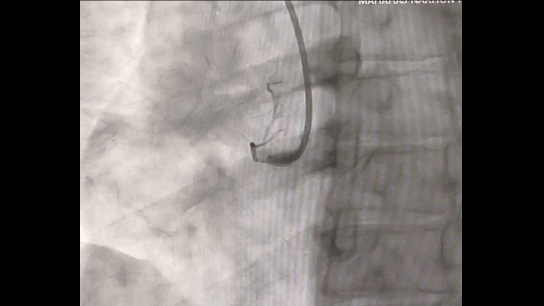

Coronary angiography reveals an obstruction in the right coronary artery (RCA).